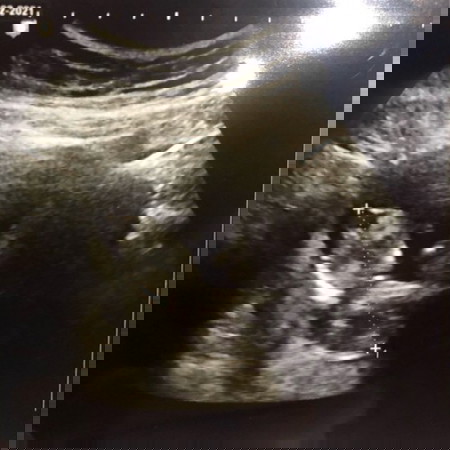

รกเกาะต่ำ ท้องแรก

14.8.63 ไปอัลตร้าซาวด์ครบ3เดือนค่ะ บี๋มีแขนมีขาครบค่ะ คุณหมอบอกว่ารกเกาะต่ำ อาจมีเลือดออกได้ ช่วงนี้งดมีเพศสัมพันไปก่อนนะคะ อยากถามแม่ๆบ้านอื่น มีใครท้องแรกและท้องอ่อนแล้วรกเกาะต่ำแบบนี้บ้างไหมคะ? กลับมาบ้านก็เริ่มมีคำถามว่า แค่ให้งดมีเพศสัมพันแค่นั้นใช่ไหมคะ หรือให้ระวังอะไรมากกว่านี้ไหมคะ? แล้วรกจะไปอยู่ระยะปกติไหมคะ? แอบกังวลกลัวหลุดจังค่ะ